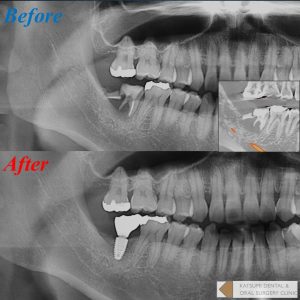

写真に示す症例では、歯周炎によって広範に骨吸収をきたし、通常の抜歯ではおそらくインプラント埋入自体が極めて困難になった可能性がありますが、本術式を選択することによってしっかり骨が回復している様子が分かると思います。本症例で使用した骨補填材リフィット®は材料の性質上レントゲン像はやや透過性を示しますが、骨質的には良好ですのでご安心ください。1年程度で骨様の所見となります。